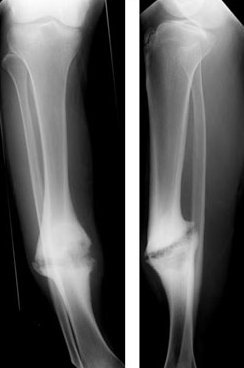

The most serious form is an infected joint - it occurs in all the above-mentioned forms and can lead to limb amputation. A special example is the tibial joint in fractures of the lower leg, where the fibula heals earlier and acts as a spacer (similarly, earlier healing of the ulna acts in fractures of the radius.